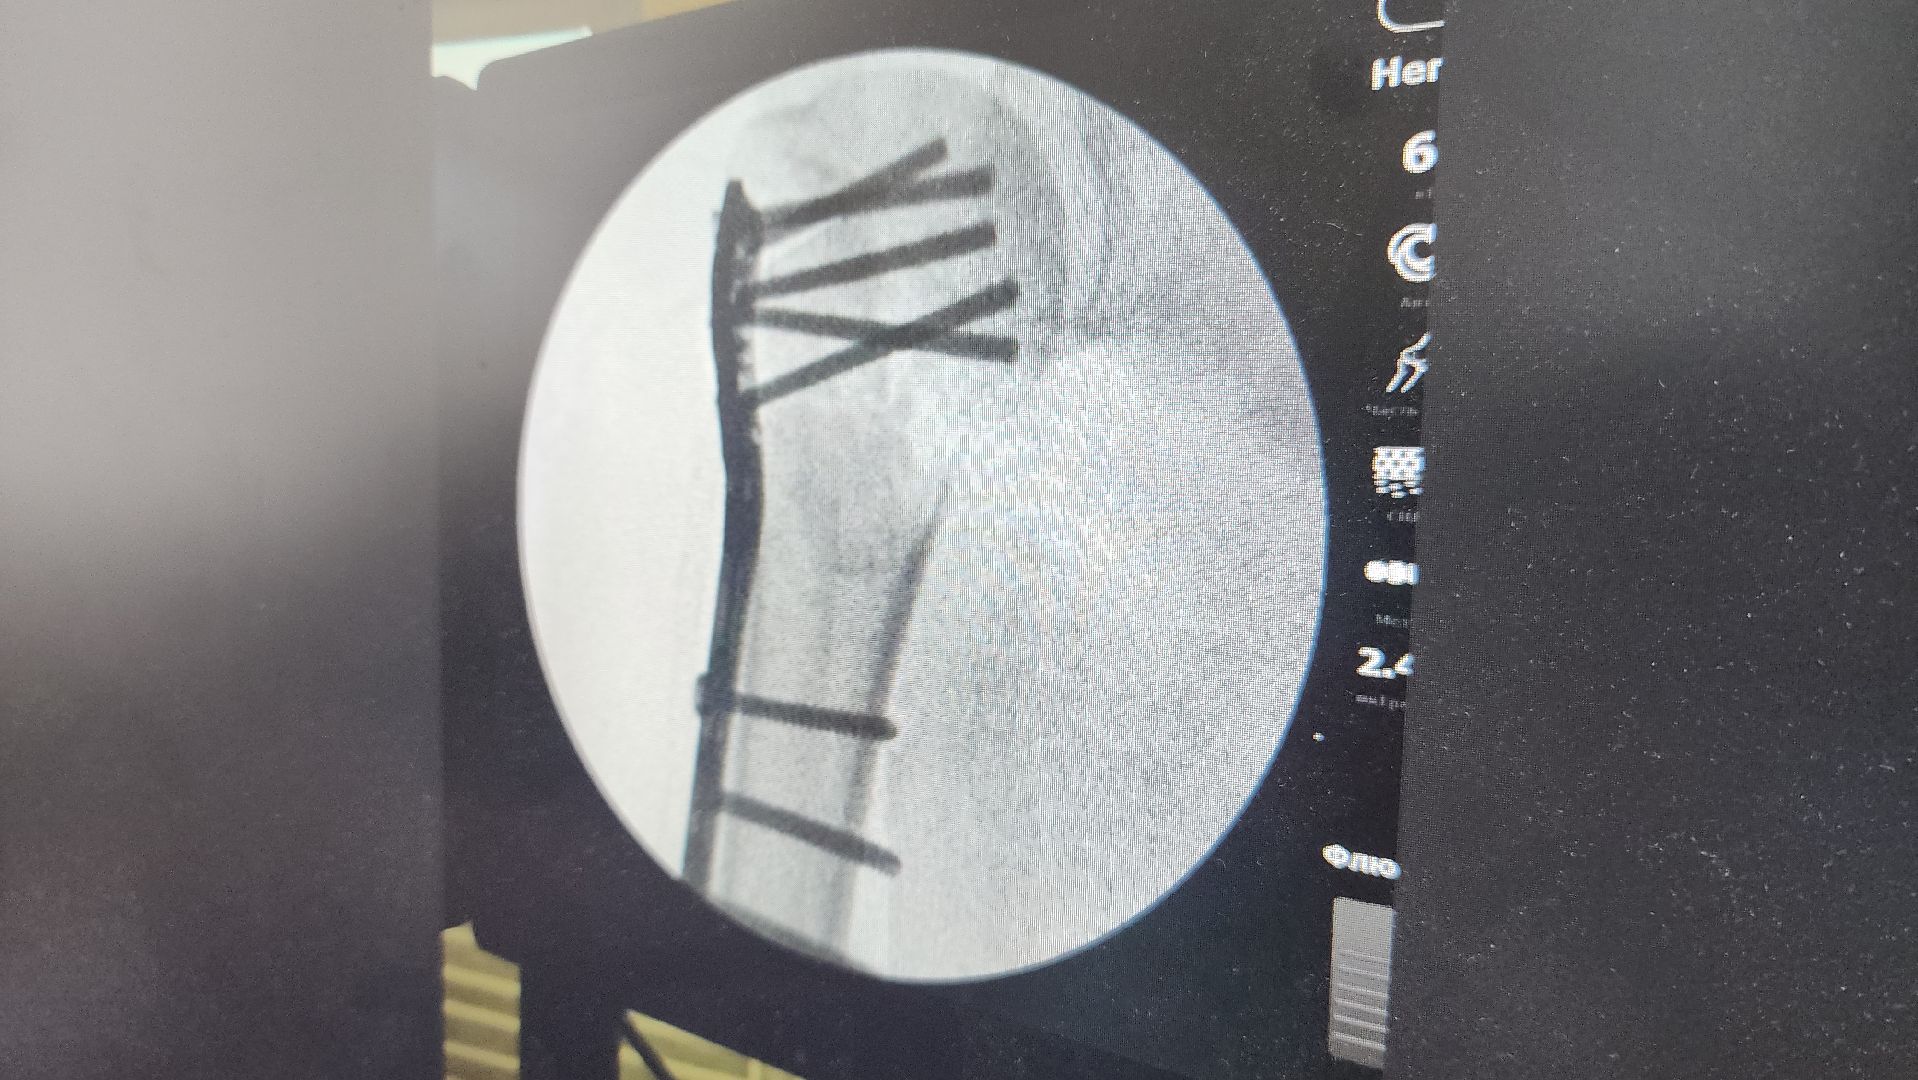

Лариса (имя изменено) обратилась за медицинской помощью не сразу после травмы, которая оказалась довольно серьёзной: оскольчатый перелом с отрывом головки кости. Всё это вкупе значительно усложняло задачу врачам. Заведующий травматологическим отделением Василий Козлов оказался перед сложным выбором: либо оперировать по стандартному протоколу, либо как-то решать вопрос с протезированием. Первое однозначно вело пациентку к инвалидности, второе требовало времени, ведь такие операции делают по квотам в специализированных центрах. И то, и другое врачи волоколамской больницы посчитали нецелесообразным и провели довольно редкую операцию.

У пациентки взяли часть костного материала из тазовой кости и по кусочкам собрали плечо, осколки закрепив между собой штифтами и пластинами. В итоге Лариса уже пошла на поправку, спустя неделю после операции её выписали, и в дальнейшем ей предстоит реабилитация. Сама женщина не знает, как благодарить врача. С её слов, он спас ей не только руку, но и жизнь.